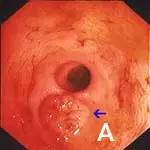

Compared to other alimentary tract organs, the duodenal mucosa has a more granular texture, due to its prominent villous architecture. Duodenal and jejunal mucosa color varies from pale pink to tan in animals having recent biliary secretion. Submucosal lymphoid aggregates appear as oval, slightly depressed mucosal structures present along the descending duodenum (in dogs) and should not be interpreted as mucosal lesions. Other normal mucosal structures include the major duodenal papillae (present in the dog and cat) and minor duodenal papillae (present only in the dog) (Figure 1).

Endoscopic appearance of the normal proximal duodenum in a dog. A lymphoid aggregate (A, arrow) is clearly visible along the lateral mucosal wall. This structure should not be biopsied as such samples confound histologic determination of lymphocytic enteritis. The major duodenal papilla (B, arrow) and a linear mucosal erosion caused by passage of the endoscope through the cranial duodenal flexure are shown in B.